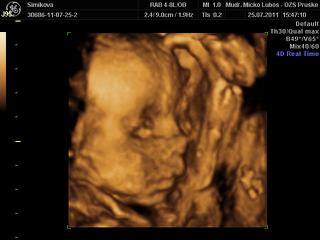

dnes som sa objednala na 3D do hlohovca, som strasne zvedava a nedockava co cakame, hned mi dali termin 9cakala som , ze budem 3tyz cakat), ale ideme uz vo stvrtok. Som zvedava, niako niesom nadcena 3Dckami, sa mi foto deticiek nepaci, take stlacene kadejake.... ani s malym som nebola, ale u neho som vedela, ze chlapec to bude, no tento pocit, ze neviem ma nici, nic si nemozem chystat 😝

@lenka1108 jeziiis lenik, ten je rozkosny, naozaj sa krasne ukazal.. 🙂 ukazovala som aj drahemu, tiez sa mu velmi pacilo 😎 😎